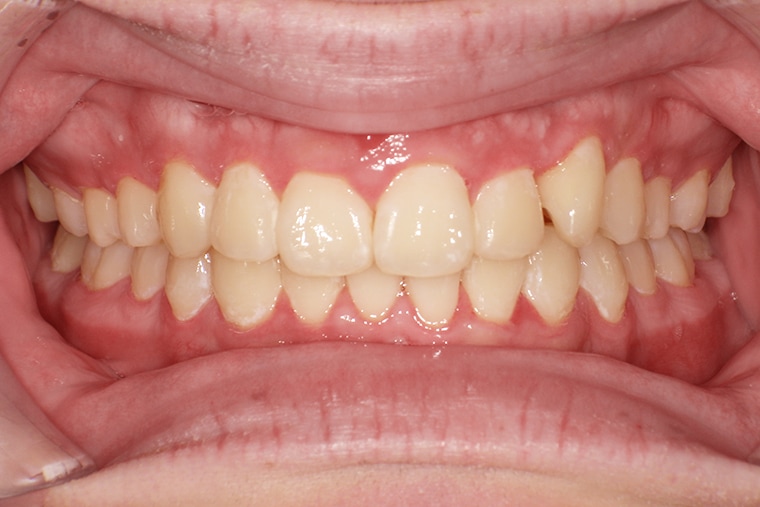

AFTER